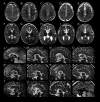

Results: Characteristic neuroimaging features included corpus callosum anomalies (82%), thickening of the fornix (74%), simplified gyral pattern (56%), enlargement of inner CSF spaces (44%), hypoplasia of basal ganglia (38%), and hypoplasia of frontal lobes (29%). We observed a marked, filiform thinning of the rostrum as recurrent highly typical pattern of corpus callosum anomaly in combination with distinct thickening of the fornix as a characteristic feature. Thickening of the fornices was not reported previously in FOXG1 syndrome. Simplified gyral pattern occurred significantly more frequently in patients with early truncating variants. Higher clinical severity scores were significantly associated with higher neuroimaging severity scores. Modeling of Foxg1 heterozygosity in mouse brain recapitulated the associated abnormal cerebral morphology phenotypes, including the striking enlargement of the fornix.

Interpretation: Combination of specific corpus callosum anomalies with simplified gyral pattern and hyperplasia of the fornices is highly characteristic for FOXG1 syndrome.